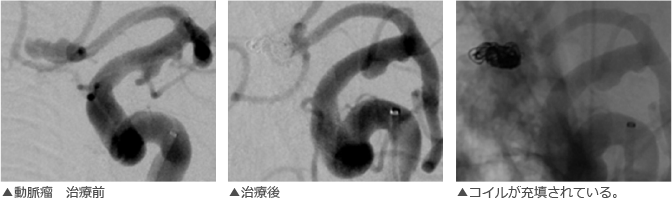

02脳血管内手術(カテーテル手術:脳動脈瘤コイル塞栓術)

極小のプラチナコイルがマイクロカテーテルを経由して脳動脈瘤に導かれます。コイルは柔軟性に富むため、脳動脈瘤の形状に沿って留置されます。 脳動脈瘤はコイルで充填されて、脳動脈瘤内部への血流を防ぎます。

実際のカテーテル治療画像